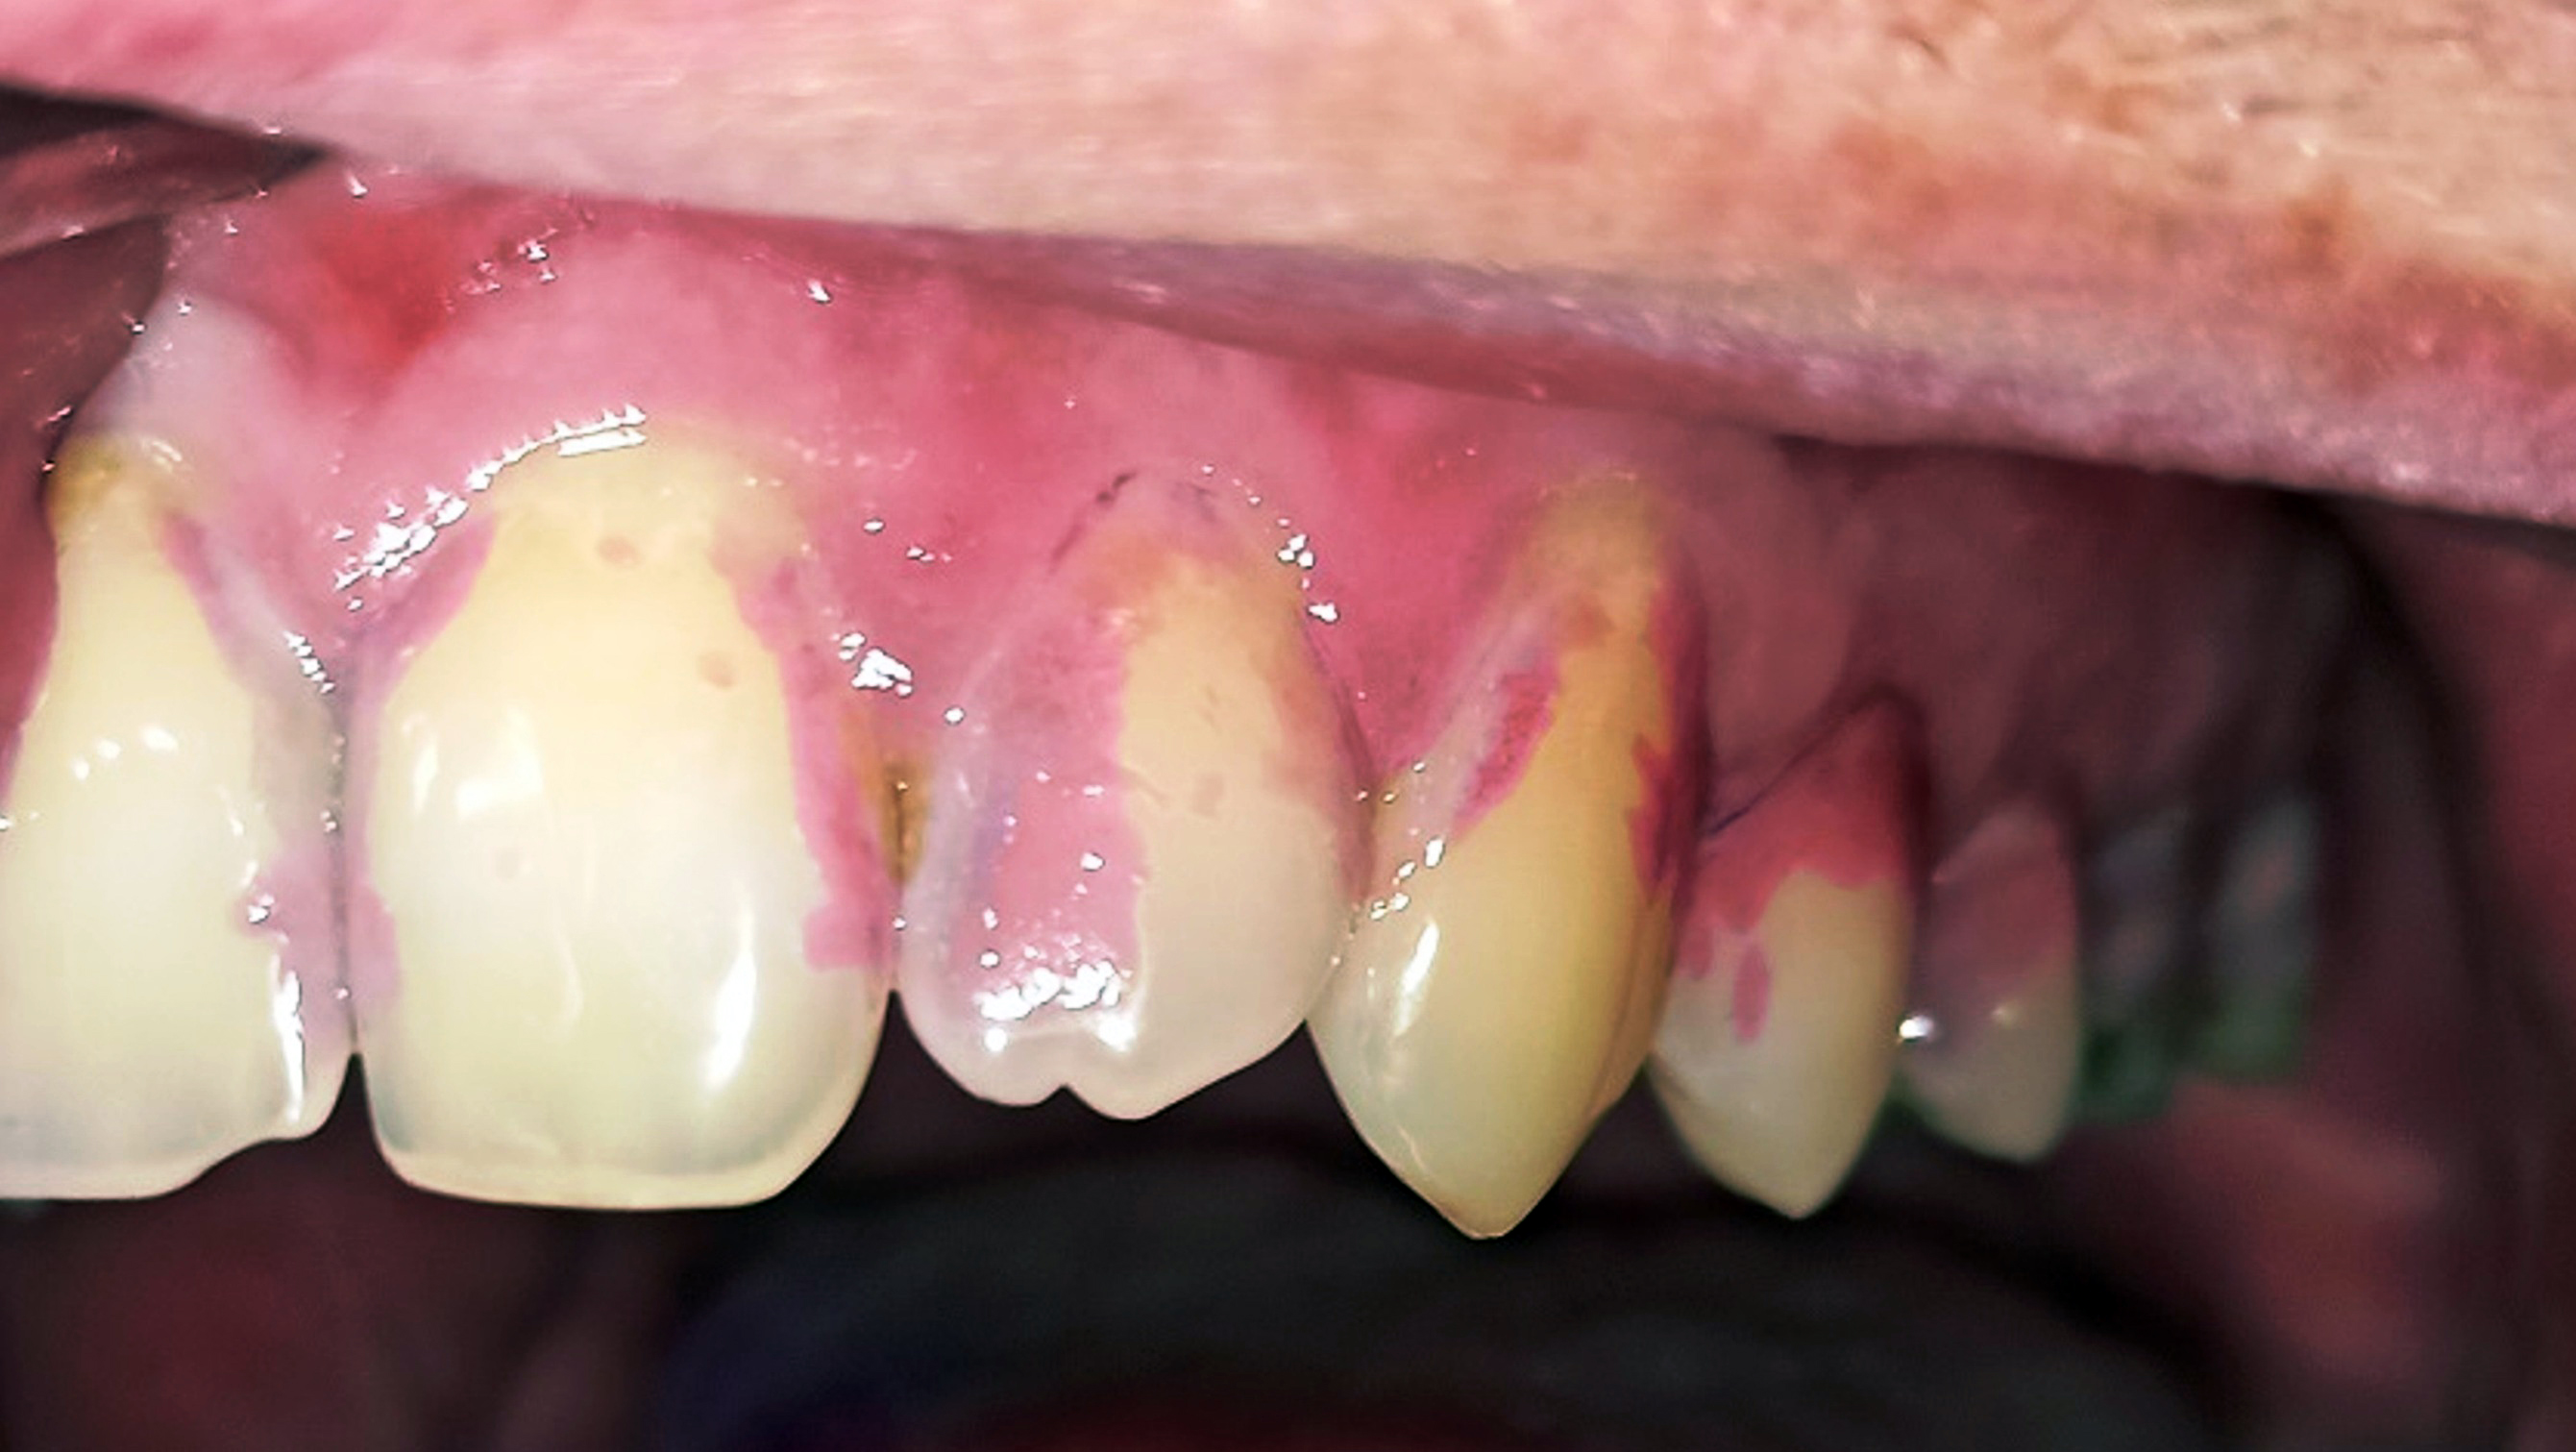

Innerhalb der Gruppe der Patienten mit Fazialisparese wurde außerdem ein Vergleich der Mundgesundheit zwischen beiden Mundhälften durchgeführt. Dabei wies die paretische Seite eine signifikant höhere Plaque-Kontamination, mehr Blutungen und höhere PSI-Werte auf als die nicht paretische Seite (Tab. 3). Die Plaque-Kontamination war in Bezug auf den API auf der paretischen Seite um 10,9 % (p = 0,004) höher als auf der nicht paretischen Seite. Ebenso wiesen die vestibulären Zahnoberflächen der paretischen Seite mehr Biofilm auf als die der nicht paretischen Seite (p = 0,002; s. Tab. 3, Abb. 2a und b). Dabei war der Unterschied bei den männlichen Patienten (0,8 vs. 0,5; p = 0,001) größer als bei den weiblichen Patienten (0,6 vs. 0,4; p = 0,002). Außerdem wurde bei Patienten mit rechtsseitiger Fazialisparese ein größerer Seitenunterschied (0,7 vs. 0,5; p < 0,001) dokumentiert als bei Patienten mit linksseitiger Fazialisparese (0,5 vs. 0,4; p = 0,043). Ursächlich erschien die Händigkeit der Patienten. Während bei Patienten mit linksseitiger Fazialisparese die Erkrankung auf der für Rechtshänder besser zu reinigenden Mundhälfte vorlag, waren rechtshändige Patienten mit rechtsseitiger Fazialisparese einer doppelten Belastung ausgesetzt (18). Die Gingivablutung nach Sondierung war auf der paretischen Seite ebenfalls signifikant höher als auf der nicht paretischen Seite (s. Tab. 3). Das spiegelte sich sowohl bei den Werten des SBI (s. Tab. 3, Abb. 3) als auch bei den Werten des PBI (s. Tab. 3, Abb. 4a und b) wider. Die Sondierungstiefen waren auf der paretischen Seite im Vergleich zur nicht paretischen Seite tiefer und der Attachmentverlust war höher. Dabei konnte jedoch kein signifikanter Unterschied nachgewiesen werden. Der mittlere PSI erreichte auf der paretischen Seite signifikant höhere Werte als auf der nicht paretischen Seite (p = 0,032; s. Tab. 3), was auf eine schlechtere Gingivagesundheit hinweist. Darüber hinaus war die Prävalenz unbehandelter kariöser Läsionen auf der paretischen Seite höher als auf der nicht paretischen Seite (s. Tab. 3). Ein Fallbeispiel illustriert eindrucksvoll die Unterschiede zwischen der kariesfreien nicht paretischen Seite und der paretischen Seite mit multiplen aktiv kariösen Läsionen (Abb. 5a und b). Zusätzlich wies die paretische Seite eine höhere Anzahl an Restaurationen auf als die nicht paretische Seite (s. Tab. 3). Hinsichtlich des Zahnsteinbefalls wurden auch im Seitenvergleich der Mundhälften keine signifikanten Unterschiede zwischen den paretischen und den nicht paretischen Seiten festgestellt. Im Einzelfall wurden jedoch eindrucksvolle Unterschiede zwischen den Mundhälften deutlich (Abb. 6a und b).